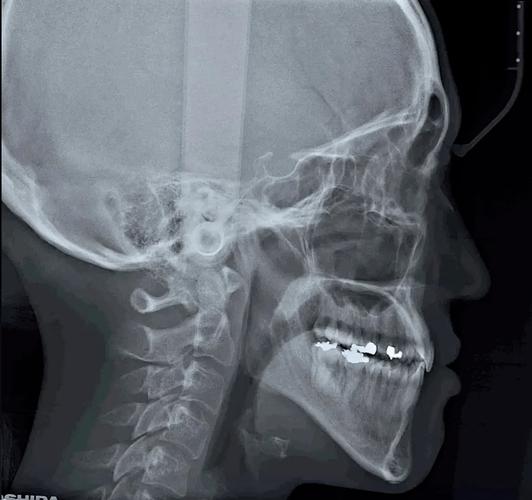

头颅侧位片是正畸诊断中至关重要的影像学检查,它提供了骨骼结构、牙齿位置、面部软组织轮廓以及气道等多维度的信息,是制定正畸治疗计划的基础,拍摄时精确的定位是获得可靠诊断信息的关键。

📐 七、 头影测量分析

拍摄完成后,正畸医生会在头颅侧位片上标记特定的解剖标志点(如鼻根点、耳点、眶点、上牙槽座点、下牙槽座点、下颌角点、颏点等),然后连接这些点形成参考平面和测量线段,通过测量这些线段的角度、距离和比例,进行全面的骨骼、牙齿和软组织分析,为诊断和治疗设计提供量化依据。